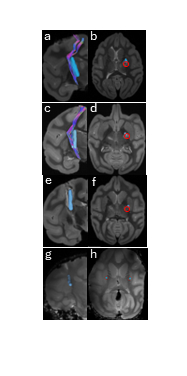

We have developed a novel, minimally invasive stereotaxic method for the precise deployment of 1.3 mm diameter scaffolds within the IC of non-human primates (NHPs). Our approach utilizes a clinically available stereotactic robot (ROSA, ZimmerBiomet) combined with a linear cannula system (AlphaOmega) to plan scaffold placement. Then, we attempted to deploy scaffolds devices into thermally coagulated lesions in NHPs (n=2) and simulated lesions within hydrogel phantoms (n=2). Post-implant MRI, co-registered with high-resolution diffusion tensor imaging were applied to check for scaffold placement accuracy (n=4). We further complement the scaffold placement method by using a novel neurosurgical microrobot (Robeauté) designed for navigation along 3D nonlinear curves, with accuracy confirmed by CBCT imaging in phantom tests.

Our implantation methods accurately placed scaffolds in the intended locations and orientations, aligning with CST fibers in both phantom models and NHP brains. The deviation angle between the scaffold and CST fibers was 17.83° (SD 6.71°, n=3). The scaffolds were precisely positioned within the IC, validating our approach. Our robot-guided method accurately steered them to their intended position, demonstrating minimal errors in targeted white matter regions.